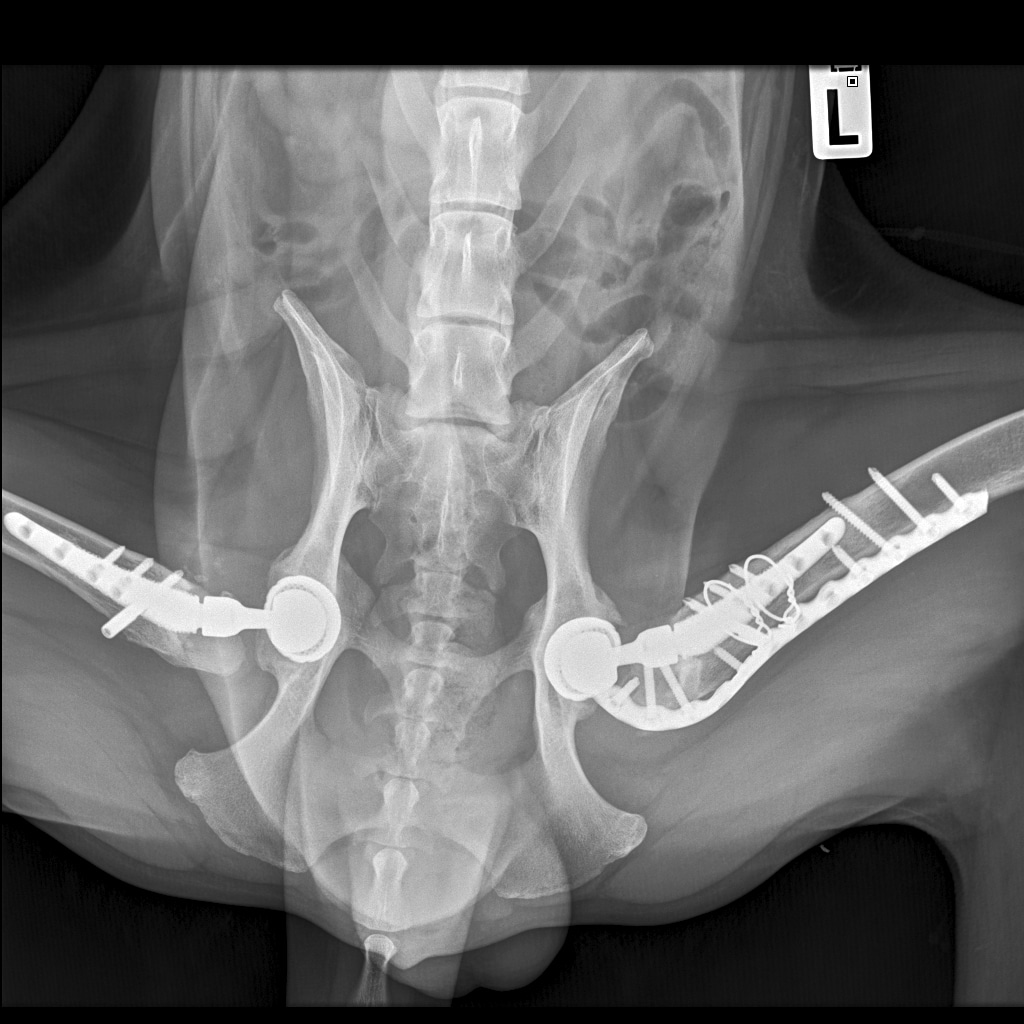

По рентгену чисто

В понедельник КТ